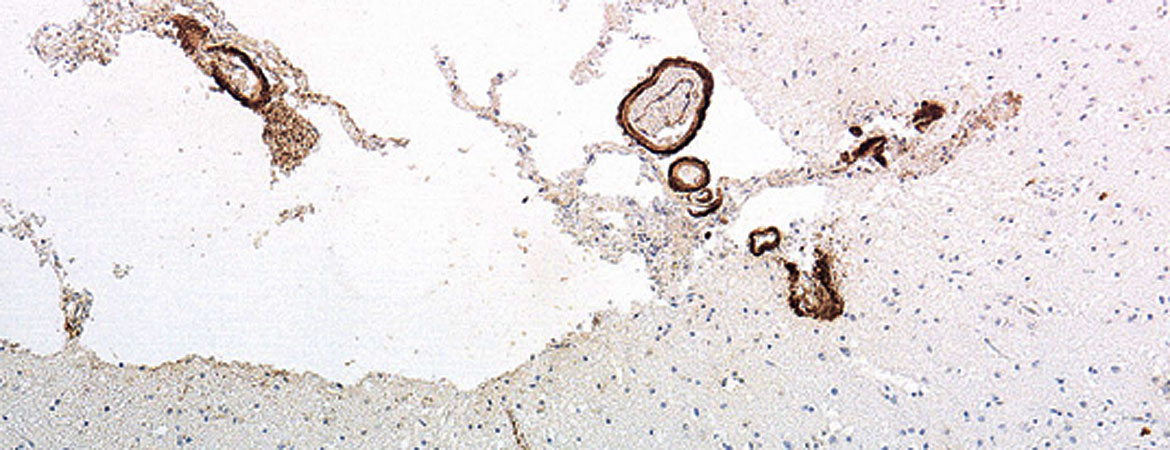

Karl Frontzek, Mirjam I. Lutz, Adriano Aguzzi, Gabor G. Kovacs, Herbert Budka (Author) Amyloid-β pathology and cerebral amyloid angiopathy are frequent in iatrogenic Creutzfeldt-Jakob disease after dural grafting Fulltext PDF Fulltext HTML